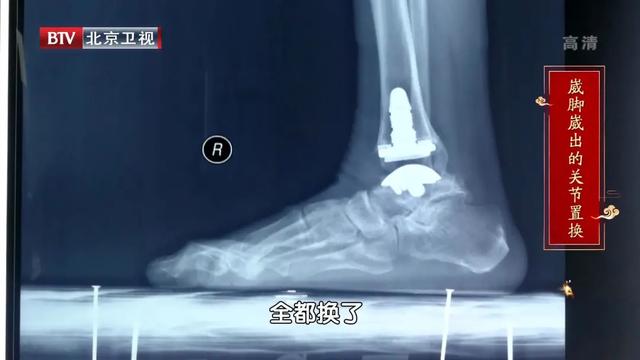

恒叔叔,71岁,无意中感觉右脚不吃力了,时不时的就会崴脚,即便自己已经很小心了,一年还是能崴脚七八次!右脚发生严重变形,穿袜子穿鞋都困难,直到出现无法缓解的疼痛,恒叔叔才到医院去治疗,医生告诉他只能做踝关节全置换,才能彻底解决问题。

髋、膝、踝应该在一条直线上,脚踝是基础,任何足部的变形都会影响到整个身体的稳定。恒叔叔就是经常崴脚导致足弓塌陷,久而久之就更容易崴脚,最后足踝变形不得不置换踝关节。